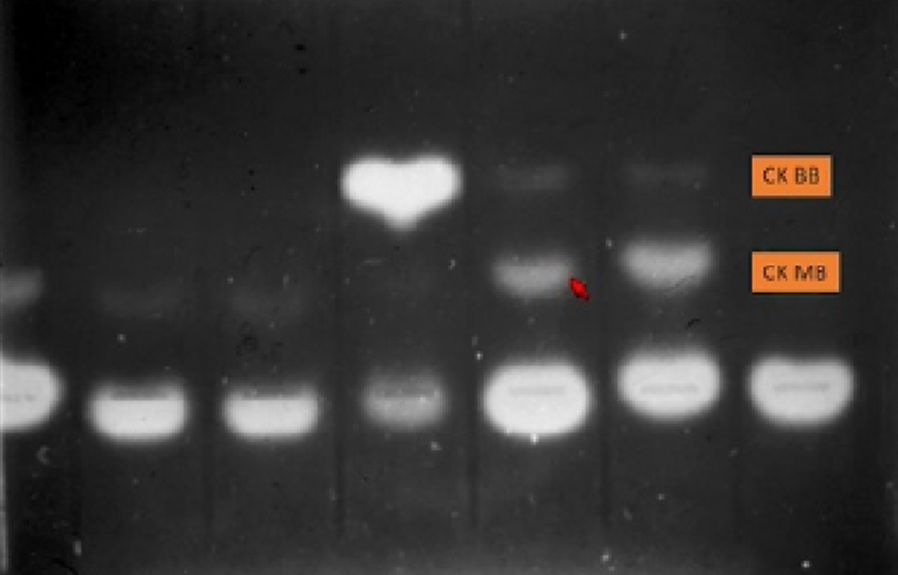

The innovation of biomarkers is a major challenge for immunoassay. The antibody's ability to accurately "capture" the marker antigen determines whether prompt detection is possible from patient samples. Thirty years ago, CK and its isoenzyme CK-MB played the role of "golden capturer" in the diagnosis of myocardial infarction.

False positive results of CK-MB obtained from an

experiment in the 1980s.

The hear-shaped stripe was a creative representation derived from the scientists' special

treatment to the gel.

This old capturer from skeletal muscle was prone to causing false positive results due to its low specificity, which often interfered with diagnosis. In the 1990s, cardiac troponin I (cTnI) started to draw attention for its excellent performance in diagnosis. It was then that HyTest became an early pioneer in cTnI research.

In 2004, HyTest's cTnI complex material was chosen by AACC as a raw material for the international troponin standard. HyTest's unceasing research progress is accompanied by the industry's increasing understanding of troponins. With its superior sensitivity and specificity, this "new challenger" is gradually replacing CK and CK-MB as the gold standard for myocardial detection.